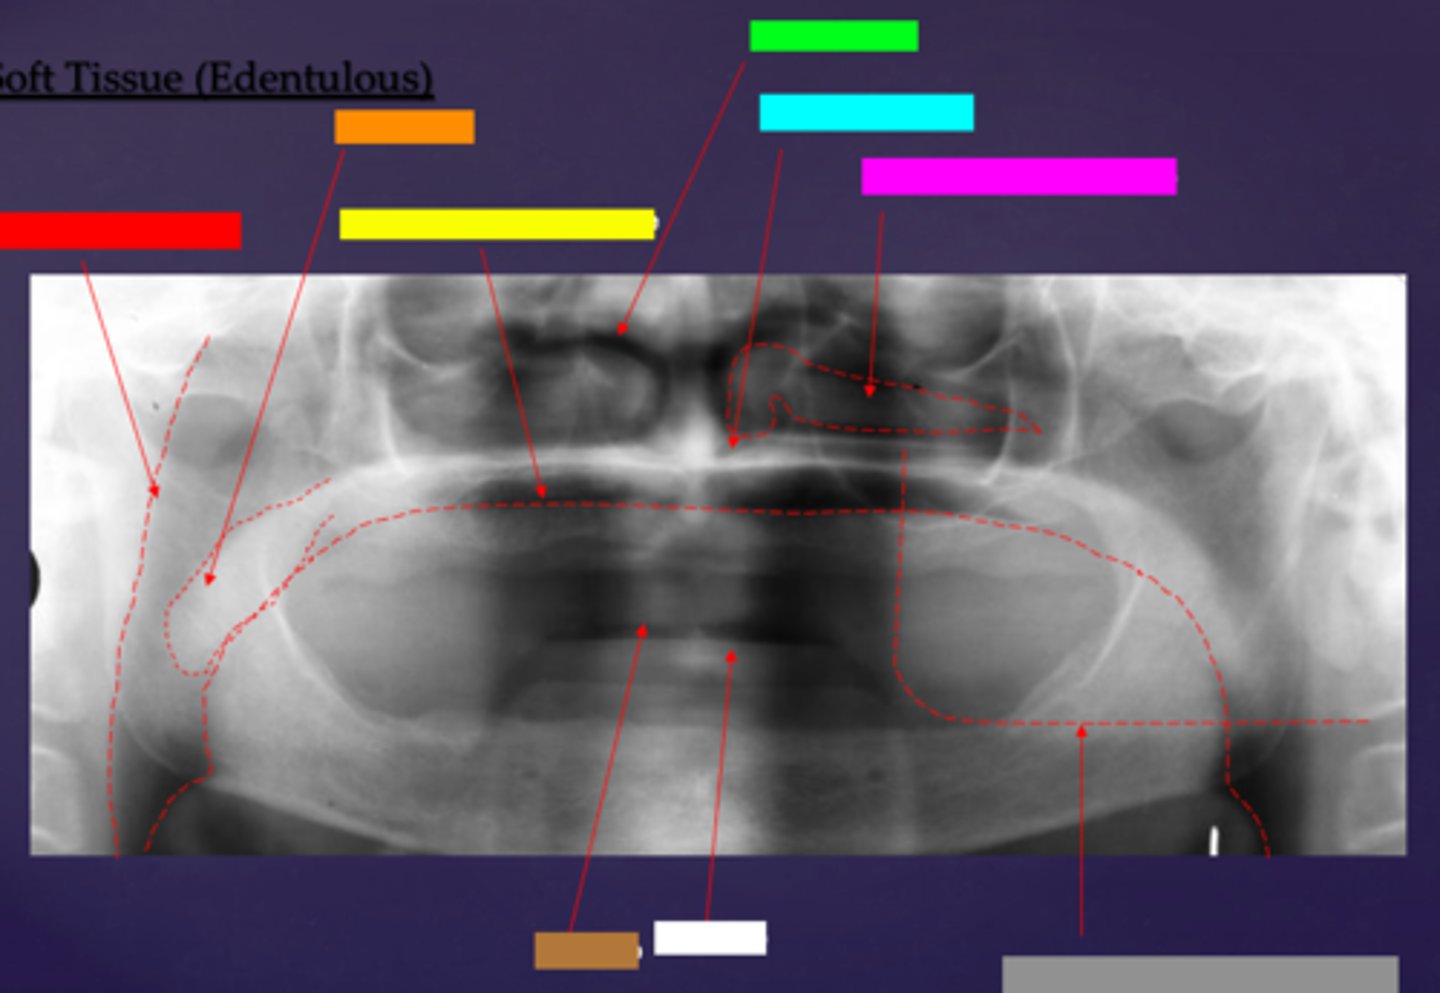

ID the soft tissue anatomy indicated by the arrow pointing from the red box:

posterior pharyngeal wall

ID the soft tissue anatomy indicated by the arrow pointing from the orange box:

soft palate

ID the soft tissue anatomy indicated by the arrow pointing from the yellow box:

dorsal surface of tongue

ID the soft tissue anatomy indicated by the arrow pointing from the green box:

middle nasal meatus

ID the soft tissue anatomy indicated by the arrow pointing from the light blue box:

inferior nasal meatus

ID the soft tissue anatomy indicated by the arrow pointing from the hot pink box:

inferior nasal concha (turbinate)

ID the soft tissue anatomy indicated by the arrow pointing from the brown box:

upper lip

ID the soft tissue anatomy indicated by the arrow pointing from the white box:

lower lip

ID the soft tissue anatomy indicated by the arrow pointing from the grey box:

ghost image of opposite mandible